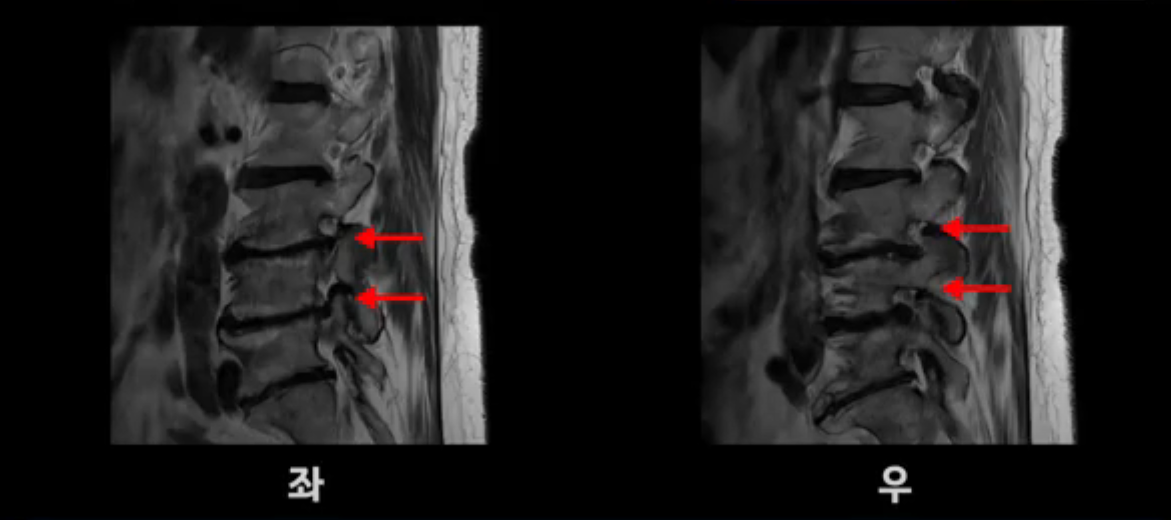

보시다시피 이 환자분은 허리 여러 마디가 다 안 좋습니다. 4마디 디스크 높이가 심하게 주저 앉았습니다.

신경이 빠져나가는 추간공들이 좌우 다 좁아져 있고

척추관도 좁아져 있습니다.

이렇게 신경 구멍들이 좁아져 있어서 신경눌림 증상이 엉덩이와 다리에 생기는데, 이런 증상들은 근육과 매우 밀접한 관련이 있습니다.